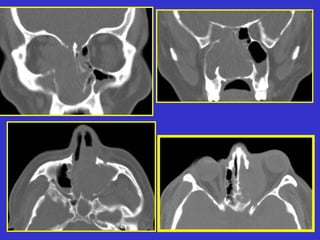

Este documento describe las diferentes proyecciones radiográficas utilizadas para examinar los senos paranasales, incluyendo las proyecciones básicas de Caldwell, Waters lateral y las proyecciones especiales como Hirtz y Waters mentonasal. También describe las diferentes estructuras anatómicas que componen el complejo ostiomeatal anterior y posterior de los senos paranasales.